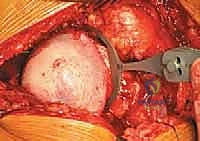

3. نحت وتشكيل رأس عظمة الفخذ

بدلاً من قطع الرأس، يستخدم الجراح أدوات ميكروسكوبية ومثاقب دقيقة جداً لإزالة الغضروف التالف وطبقة رقيقة من العظم المريض، ليتم "نحت" رأس العظمة ليصبح جاهزاً لاستقبال الغطاء المعدني بشكل مثالي.

4. تركيب الغطاء المعدني (Femoral Component)

يتم تثبيت التاج أو الغطاء المعدني الأملس فوق رأس عظمة الفخذ المنحوت، وغالباً ما يتم تثبيته باستخدام مادة أسمنتية طبية خاصة لضمان ثباته المطلق.

6. إرجاع المفصل والإغلاق

يتم إعادة رأس الفخذ المغلف بالمعدن إلى داخل الوعاء المعدني في الحوض. يقوم د. هطيف باختبار نطاق الحركة والتأكد من استقرار المفصل وعدم قابليته للخلع، ثم يتم إغلاق الشق الجراحي تجميلياً.